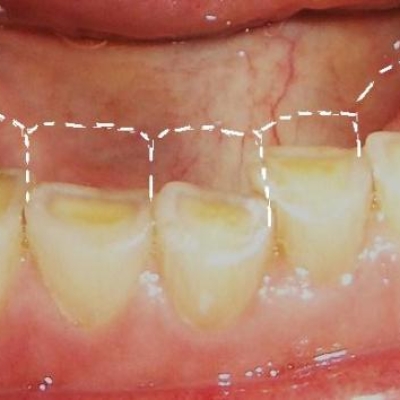

What is tooth wear?

Tooth wear also called 'Occlusal Disease' is one of the most prevalent dental problems of the modern age. This is defined as the loss of dental hard tissue(mainly enamel) caused by factors other than tooth decay or trauma. As we age the amount of wear increases on our teeth and thus...

Treatment for tooth wear

Due to the effect of tooth wear, some degree of enamel loss is always present. We follow the concept of minimally invasive treatment which means we preserve as much of your tooth structure as possible and aim to just adding 'enamel' back to the tooth. In essence you have...